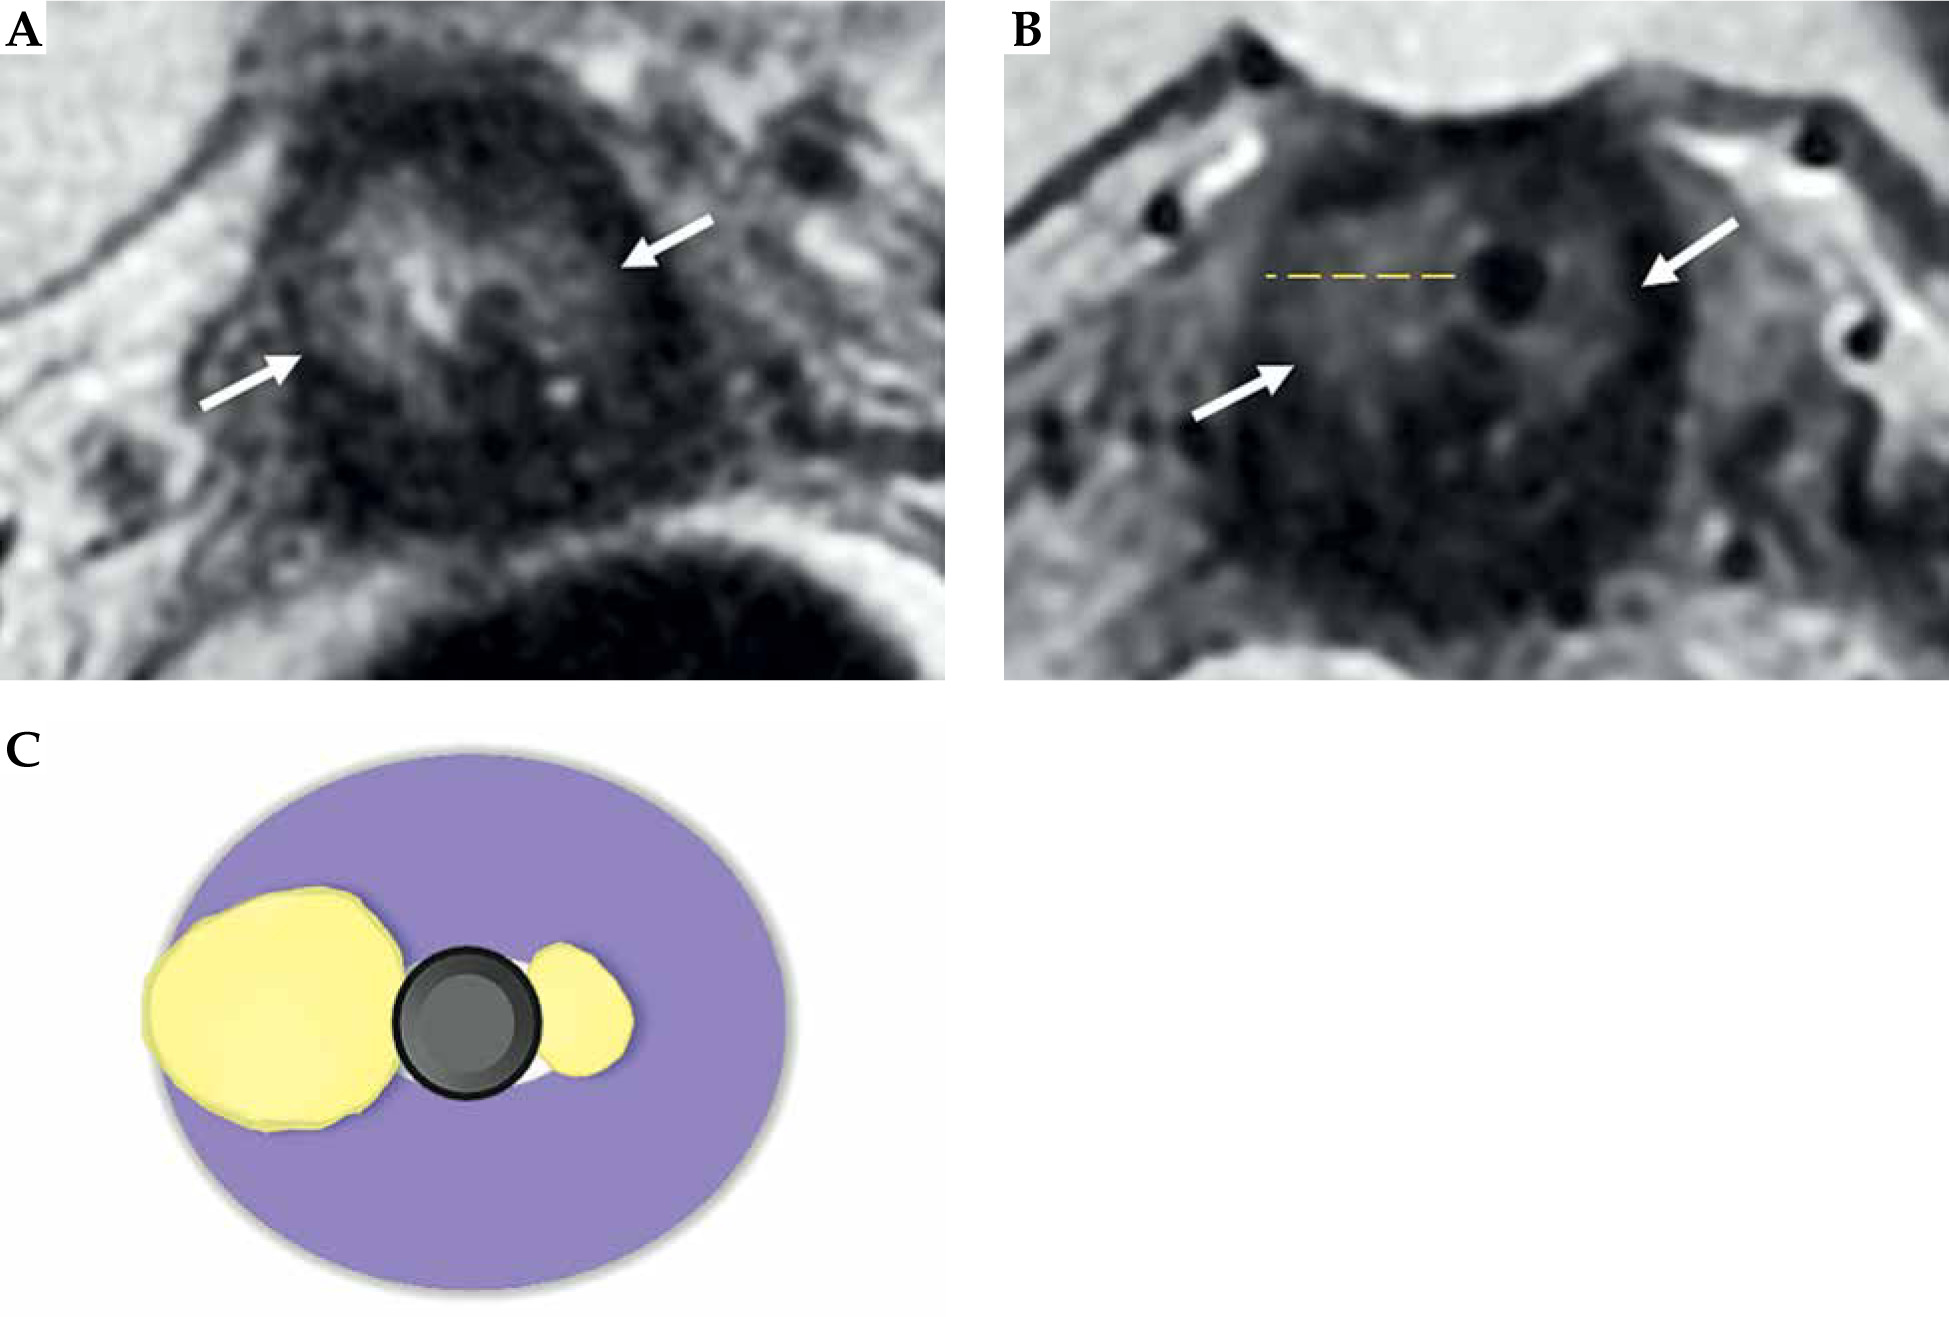

Fig. 6

31-year-old woman with squamous cervical carcinoma treated with EBRT. Post-external beam radiotherapy (EBRT) images (A, B) show reconstitution of low signal intensity of cervical stroma (arrows in B). C, D) Post-applicator MRI. Images show correct positioning of applicator within endometrial cavity (arrowhead) and ring in vaginal fornices (asterisk)

Fig. 7

59-year-old woman with squamous cervical carcinoma treated with external beam radiotherapy (EBRT). Post-EBRT images (A, B) show reconstitution of low signal intensity of cervical stroma (arrows in B). C, D) Post-applicator MRI. Images show correct positioning of applicator within the endometrial cavity (arrowhead) and ovoids in vaginal fornices (asterisk)